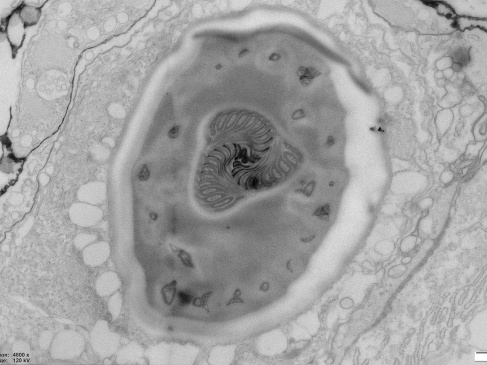

Zdjęcie wykonane przez Kierowniczkę Laboratorium Bioobrazowania na Wydziale Biologii UG dr hab. Magdalenę Narajczyk, zostało wyróżnione jako jedno z dziesięciu najlepszych zdjęć w konkursie fotograficznym Bio-Art: „The beauty behind biological sciences”, zorganizowanym przez FEBS (Federation of European Biochemical Societies).

Zdjęcie wykonane przez dr…